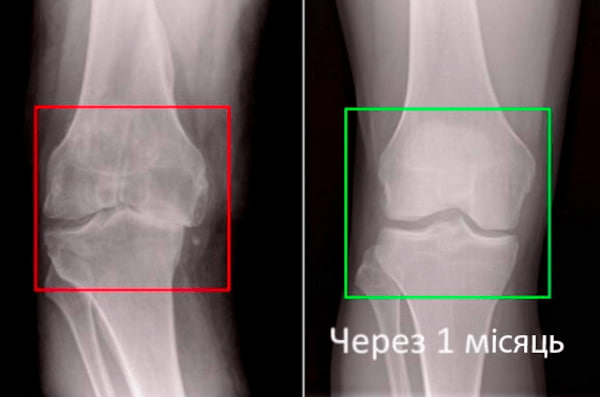

Візьміть до уваги знімок колінного суглоба 63-річного пацієнта за 1 місяць користування ArtroFLEX - суглоб повністю регенерувався.